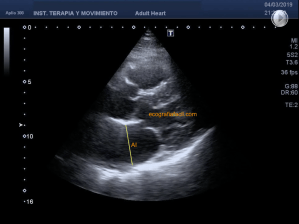

147. Ecocardiografía. Planos Subcostales.